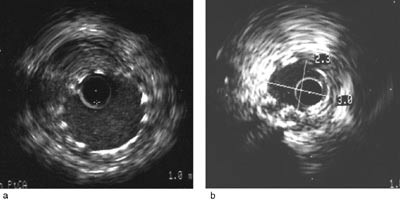

Ultralydsignalet blir reflektert ved forandring i de akustiske egenskapene til strukturene i arterieveggen. Relativt skarpt ekko får man fra intima som grenser mot lumen og fra grensesjiktet mellom ytre del av media og membrana elastica externa som grenser mot adventitia.

Intima er normalt en tynn struktur som bare vil være svakt synlig like utenfor media (fig 1). Ved fødselen er det bare ett enkelt lag endotelceller, men tykkelsen øker med alderen og spesielt i områder der veggtensjonen er høy som i arteriedelinger (5). Ved aterosklerotisk sykdom vil de ulike lag reflektere lydbølger, og intima vil fremstilles som tett, hvitt vev (fig 2 a). Media har et homogent lag med glatte muskelceller som ikke reflekterer ultralyd og som derved synes som en tynn, mørk sone med tykkelse om lag 0,2 mm. Den lave refleksjonen av ultralyd fra media kommer av at det er mindre kollagen og elastin enn i nabolagene. I grensen mellom media og adventitia er det et markert skille i ultralydrefleksjonen svarende til membrana elastica externa. Adventitia har lag med kollagen som vil reflektere mye ultralyd og som derved er hvitt på ultralydbildene. Adventitia har foruten bindevev også blodkar, lymfekar og nerver. Blodet i lumen av arterien er lettest synlig på levende bilder som beveglige, subtile ekko og disse bevegelige ekko er nyttig ved definering av grensen mot intima. Injeksjon av røntgenkontrast gjennom føringskateteret vil gjøre det lettere å skille mellom blod i lumen og intima fordi kontrasten vil inneholde mikrobobler som reflekteres.